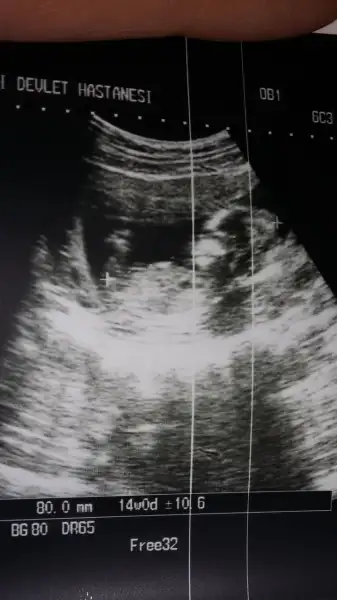

Kizlar rica etsem cinsiyetten anlayanlar benim icin yorumlayabilir misiniz? Çok tesekkur ederim. Benim doktor bu gune kadar bi yorumda bulunmadi. Ilk gebeligim oldugu icin çok merak ediyorum

Eklentiler

• Screenshot_2018-01-04-08-08-35.webp

10,5 KB · Görüntüleme: 60

• Screenshot_2018-01-04-08-08-28.webp

12,7 KB · Görüntüleme: 59

sen onu desene bedef le bende biri kız desin diye uğraşıp duruyoruz :) önce sağlık sıhhat tabii ki hepimizin yavrularına sonra da gönlünden ne geçiyorsa versin Rabbim